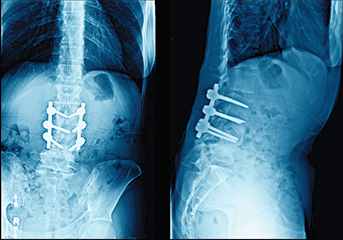

Safety in Spine Surgery

The nature of spine surgery presents surgeons with its own set of challenges. A number of initiatives are underway at NewYork-Presbyterian to address some of the most pressing issues. These include:

- Dual surgeon approach for high-risk spine cases

- Dedicated intraoperative spine team checklist that details required steps from the preoperative stage to pre-incision, to post-incision and pre-instrumentation, to postinstrumentation

- Reviewing postoperative orders with the spine dedicated ICU team

In addition, our surgeons continue to develop best practices:

Preventing Wrong Level Spine Deformity Surgery

Our spine surgeons have introduced a checklist representing a consensus on items to review before and during surgery in order to confirm the correct vertebral level.